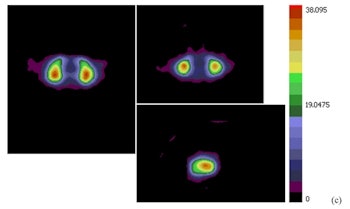

A mean binding potential image for the control group (a) has higher uptake than a mean binding potential image for the Parkinson's disease group (b). A statistically significant difference between the two was demonstrated using a student's t-test (c; t-value image).